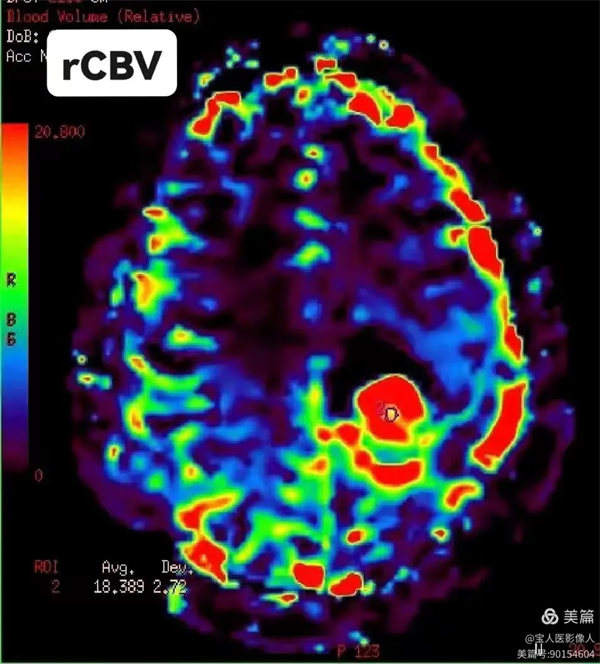

圖2:腦血容量(CBV):每100g腦組織內的血容量,單位(mL/100g)。即血容積。

DSC可獲得的參數有:局部腦血容量(regional cerebral blood volume,rCBV)、局部腦血流量(regional cerebral blood flow,rCBF)、局部平均通過時間(regional mean transit time,rMTT)、局部達峰時間(regional time to peak,rTTP),能夠提供組織詳細的灌注信息,如灌注不足、側支循環建立、血流再灌注或過度灌注等。

二、腦腫瘤的應用

1、顱腦腫瘤的診斷和鑒別診斷。

2、顱腦腫瘤的分級。